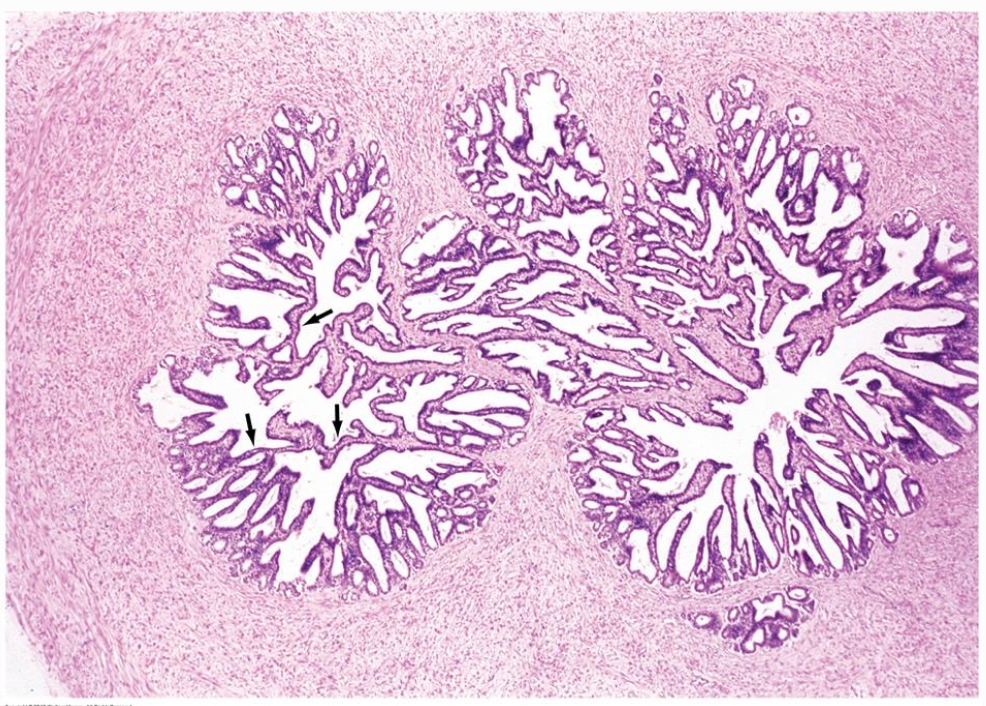

- Mukosa: starkt veckad, bildar komplex labyrint av säckar → flera tvärsnittade lumen ses i histologin.

- Epitel: flerradigt (pseudostratifierat) cylindriskt; principalceller med sekretgranula (fruktos, prostaglandiner, koagulationsproteiner) och små basalceller.

- Lamina propria av lucker bindväv med elastiska fibrer; underliggande muskularis med inre cirkulärt och yttre longitudinellt glatt muskellager.